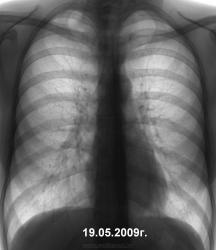

И, даже если-бы, что-то ёкнуло, или глаз "зацепился" тактически было-бы правильно писать норму. У нас было, довольно немало подобных случаев, когда мы брали на контроль, и чаще на восьмерке обнаруживали нежное снижение прозрачности легочной ткани в апико-медиальном отделе 1 сегмента. Но выявленное совершенно не нужно коллеге фтизиатру, ибо "такое" коллеги фтизиатры не берут, да и не должны брать.

В таких случаях мы имели "геморрой" только для себя, ибо пациента, для динамики довольно часто посылали для контроля, именно к нам. Конечно, не всегда, но в большинстве своём, на месте этой нежной инфильтрации в последующем очаги появлялись, но это потом. Об этом (малых изменениях) писал и коллега Лупан.

Лично для себя, в последнее время сделал вывод, и вывод этот практически правильный - диагностику тубера по флюшкам начинать с инфильтративного и не "меньше", ибо, то будут "пустые хлопоты", именно, только для рентгеновской службы.

Игорь Иванович, не терзайтесь.Видимых изменений не узрела.